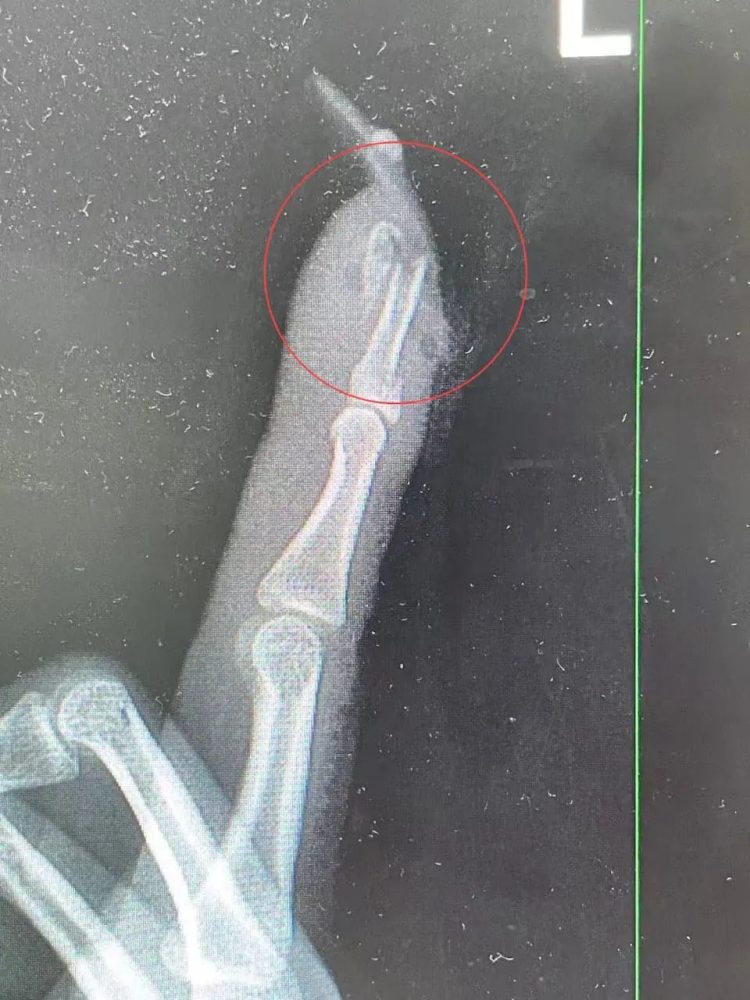

送医后,医生发现她的伤口血肉模糊,甲床严重破裂且部分外露,必须立即动手术进行复位固定。接诊的曹立副主任医师直言,若没有这片长甲片增加受力面积,伤势本不至于如此惨重。正是美甲造型的复杂与长度,在意外瞬间成了伤害手指的“凶器”。